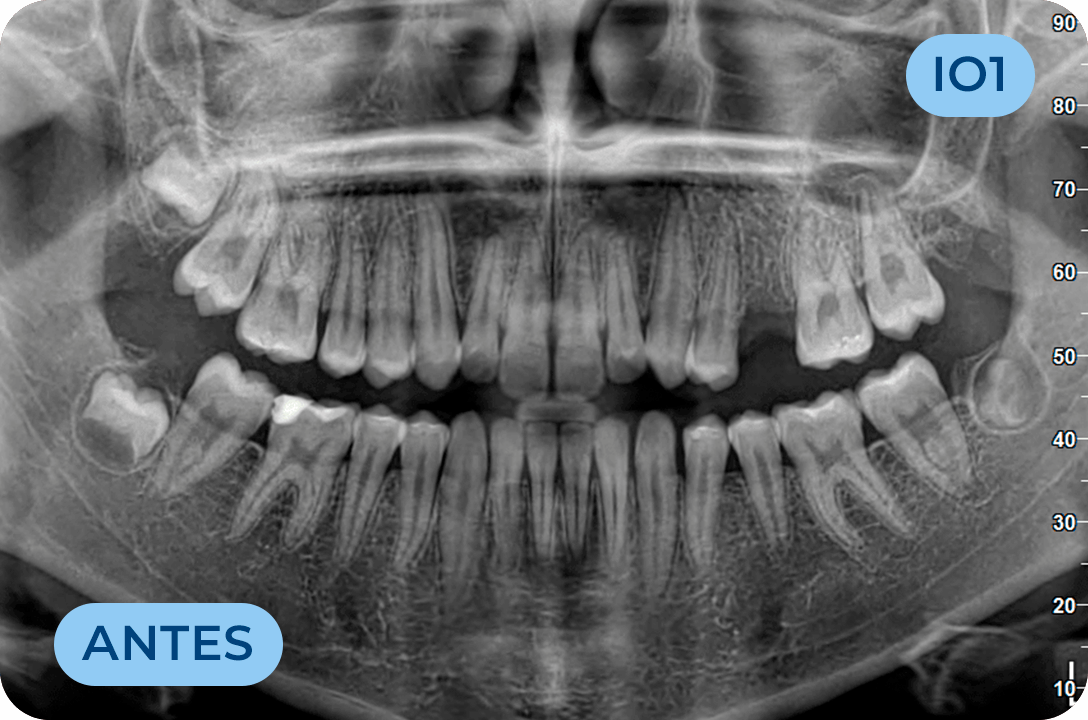

Ortodontia

É a especialidade da Medicina Dentária que se debruça sobre o estudo e correção das más posições dentárias e dos maxilares. Atualmente é possível tratar pacientes de todas as idades, no entanto a 1ª consulta deve ser realizada ainda na infância para intercetar eventuais problemas de desenvolvimento esquelético e funcional.